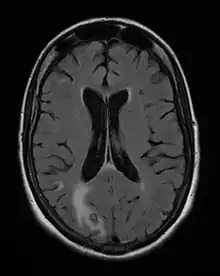

O diagnóstico da neurotoxoplasmose pode ser realizado através de exames de tomografia computadorizada ou ressonância magnética que podem revelar lesões isoladas ou múltiplas, ovaladas e com captação de contraste anelar. Exames laboratoriais de sorologia de anticorpos igG, IgM e IgA, anti-T.gondii são pouco específicos para o diagnóstico da neurotoxoplasmose; considera-se que a ausência de anticorpos IgG anti-T. gondii no soro e líquor depõe fortemente contra o diagnóstico de neurotoxoplasmose ao passo que imunoglobulinas IgA específicas no líquor e IgG na saliva podem representar dois marcadores auxiliares para o diagnóstico diferencial da encefalite toxoplásmica.[2]